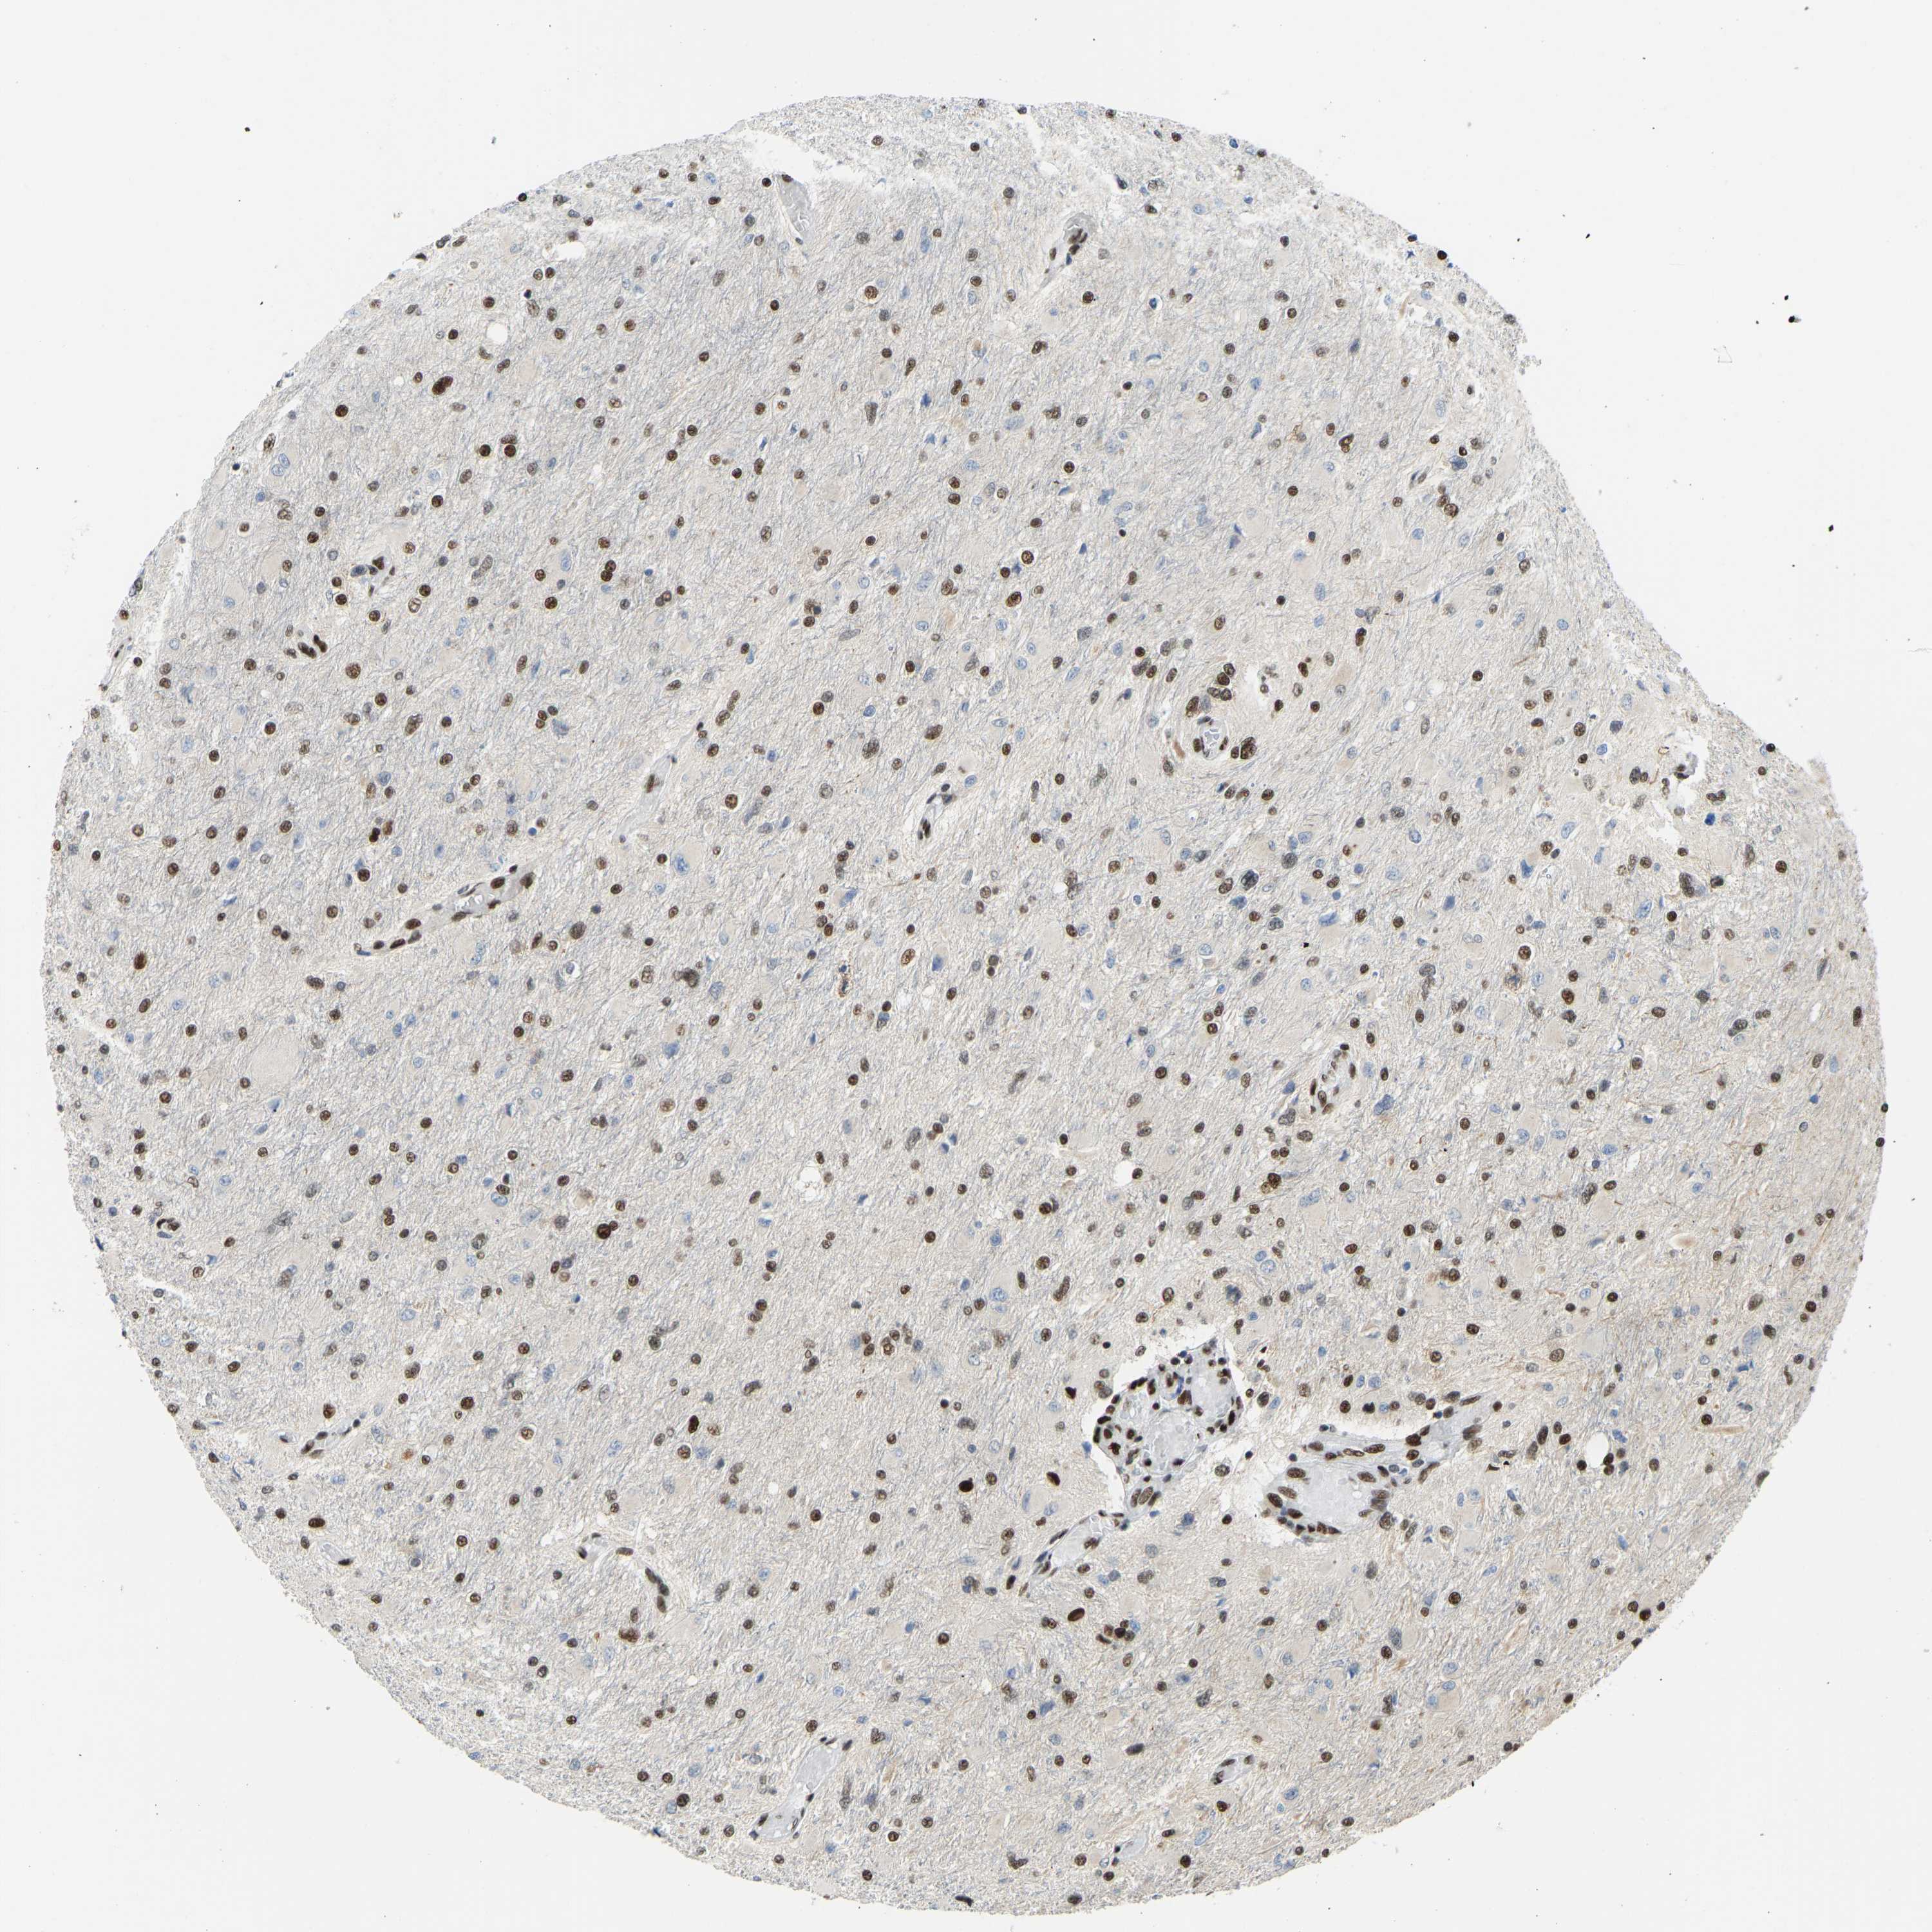

GLIOMA - Protein expressioni

A mouse-over function shows sample information and annotation data. Click on an image to view it in a full screen mode. Samples can be filtered based on level of antibody staining by selecting one or several of the following categories: high, medium, low and not detected. The assay and annotation is described here.

Note that samples used for immunohistochemistry by the Human Protein Atlas do not correspond to samples in the TCGA dataset.

Antibody stainingi

Antibody staining in the annotated cell types in the current human tissue is reported as not detected, low, medium, or high, based on conventional immunohistochemistry profiling in selected tissues. This score is based on the combination of the staining intensity and fraction of stained cells.

Each image is clickable and will lead to virtual microscopy that enables deeper exploration of all samples and also displays staining intensity scores, fraction scores and subcellular localization as well as patient and tissue information for each sample.

Antibody HPA017998

Antibody HPA018864

Staining

High

Medium

Low

Not detected

Intensity

Strong

Moderate

Weak

Negative

Quantity

>75%

75%-25%

<25%

None

Location

Nuclear

Cytoplasmic/membranous

Cytoplasmic/membranous,nuclear

Glioma, malignant, High grade

Glioma, malignant, Low grade